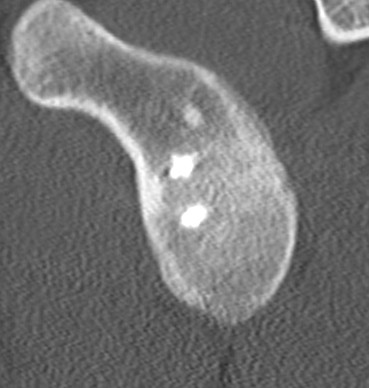

Case 1

Recurrence of instability without trauma

- anchors very high

- into glenoid face

- MRI suggests remaining inferior bankart

- no bony deficiency, no HAGL